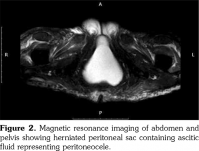

We performed extended investigations that showed normal blood albumin level. Tumor markers were significant only for an elevated serum cancer antigen 125 (CA-125) (80 U/L normal <35). Work-up for TB was negative including adenosine deaminase and polymerase chain reaction in ascitic sampling. Cytology was negative for malignant cells. We conducted computed tomography scan for the chest, abdomen and pelvis with contrast showing massive ascites with ill-defined omental thickening related to the anterior abdominal wall. A cystic lesion was seen at perineal region, minimal bilateral pleural effusion and massive abdominal ascites. Laparotomy and biopsy were performed revealing fat necrosis. Subsequently, magnetic resonance imaging of the abdomen and pelvis was conducted but it was insignificant apart from massive ascites with adhesions. No ovarian masses were observed (Figure 1). In lower perineal region, herniating peritoneal sac was noted containing ascitic fluid representing peritoneocele (Figure 2).